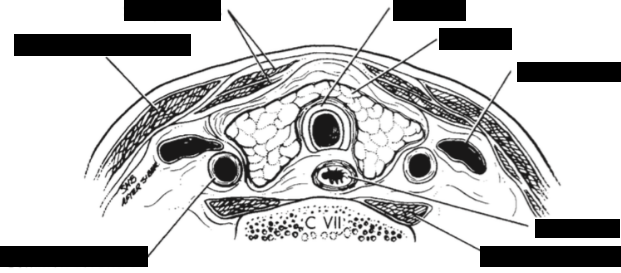

Label the image

A

Identify each structure

Describe its US appearance + location in relation to the thyroid

1. Strap muscles (anterior/ thin hypoechoic band)

2. Sternocleidomastoid m. (lateral/ oval hypoechoic)

3. Longus colli m.(posterolateral/ triangle)

4. Trachea (posterior midline/ air shadow)

5. Esophagus (posterior to left lobe/ target)

6. CCA (lateral)

7. IJV (lateral